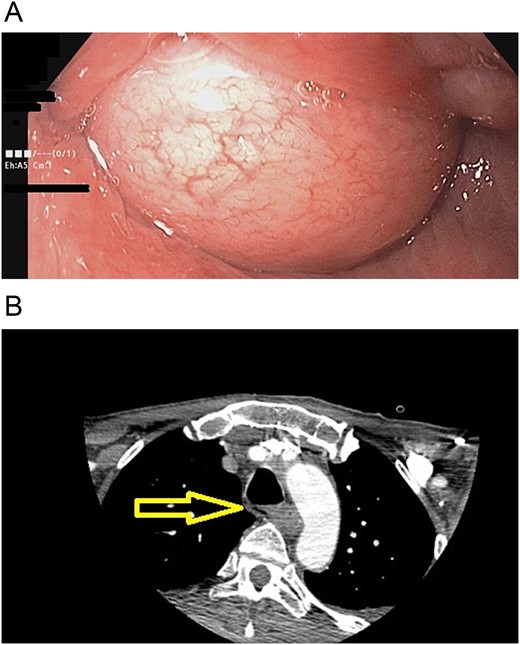

He partially recovered from the hemiplegia and neurologic sequelae, but he became completely care dependent. One thing that worsened during this time was his dysphagia; he did not have any neurogenic dysphagia; nevertheless, he was unable to drink anything, and it became so severe that he was unable to swallow saliva. Therefore, one year later, he presented to our office. A new endoscopy revealed that the giant polyp completely obstructed the lumen of the esophagus, and a new chest CT showed that the polyp grew but did not invade any surrounding structures (Fig. 2).

(A) Endoscopy, the polyp obstructs the esophagus's lumen. (B) CT scan: esophageal polyp size has increased in size over a year.